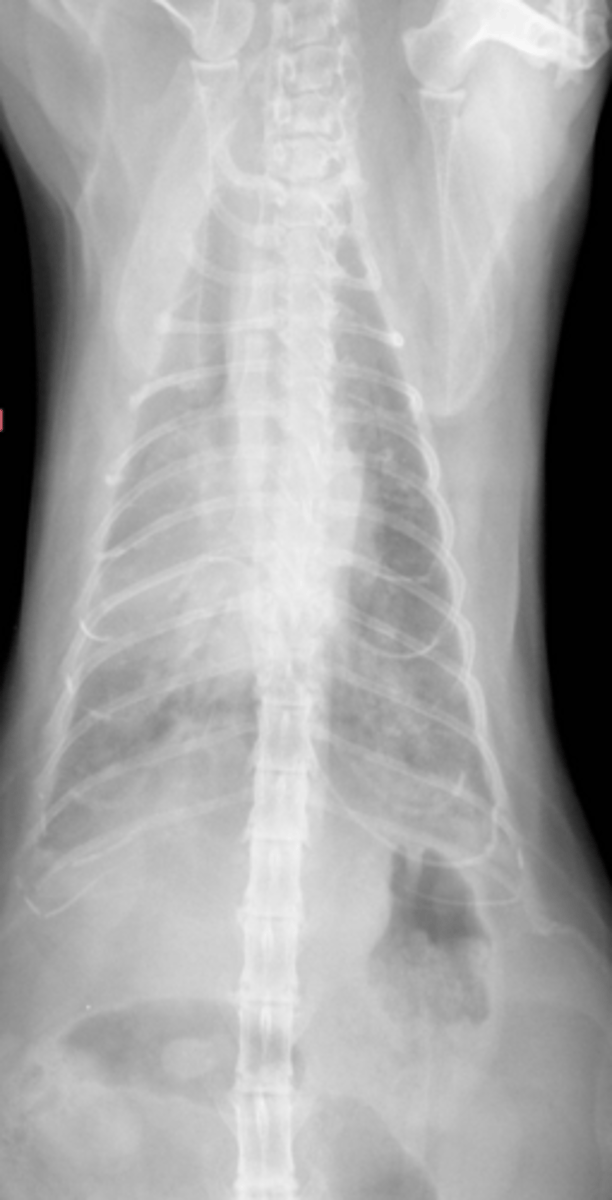

Pneumonia

-Air bronchogram

-Heart is not enlarged - 8.7

Given the following Rad what do you suspect?